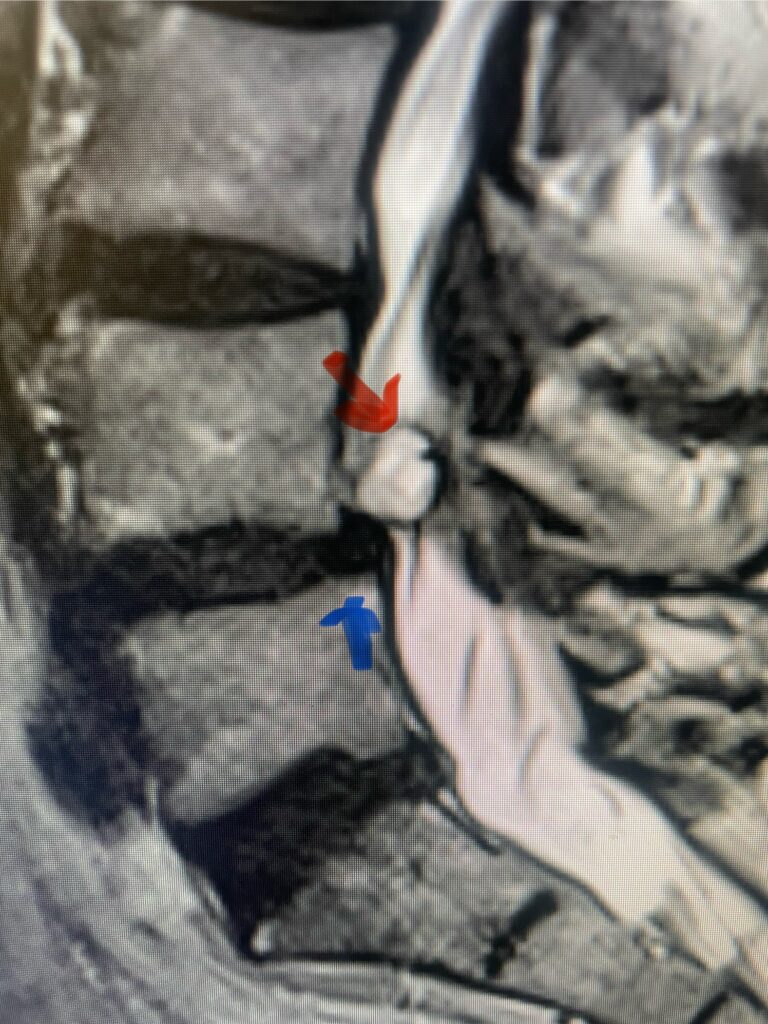

Figs 1a,b: T2-weighted sagittal and axial MRI demonstrating (red arrow) a large right L4-5 foraminal synovial cyst. Note the grade 1 spondylolisthesis (blue arrow)

This 54-year-old female with a long history of low back pain presents with three weeks of a progressive right footdrop with associated numbness and tingling of the right leg. In addition, she had right lateral hip pain down to the dorsum of her foot. She first noticed her right foot slapping the floor when she walked. She had no prior trauma or unusual activity before this began. Her chiropractor, who had treated her back pain for a long time, first noticed the foot drop and referred her for further evaluation. She presented with ⅖ strength in her right dorsiflexor. MRI revealed a large right L4-5 foraminal synovial cyst with some mass-effect on the thecal sac. (Fig. 1) She also had an associated grade 1 spondylolisthesis. Because the cyst was more foraminally-oriented, it had the majority of its effect on the right L4 nerve root. It was felt the patient required surgery to attempt to reverse her weakness. We performed a decompressive laminectomy at L4, removing the inferior facet process on the right in order to gain lateral and foraminal access to the right L4 nerve root. In the lateral recess there was a heap of inflammatory tissue which we entered, revealing the cyst. The medial wall was stuck to the dura. We internally decompressed the cyst which was mainly gelatinous material with some fluid. We dissected and removed as much of the cyst we could safely remove but left the medial wall for fear of removing it would cause a CSF leak, upon removing the bulk of the cyst we encountered anteriorly the descending and exiting right L4 nerve root which was purplish in color and clearly inflamed. We performed a generous foraminotomy of the right L4 as well as the right L5 nerve root. We also performed an instrumented fusion at L4-5 (Fig. 2).